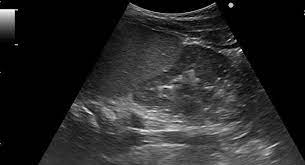

Dromedary Hump Of The Left Kidney Sono Gallery

Dromedary Hump Of The Left Kidney Sono Gallery from i.vimeocdn.com

They have also been introduced to arid regions of central. Add a dromedary hump photo. Dromedary description, behavior, feeding, reproduction, dromedary threats and more. Dromedary hills — the dromedary hills are an area of morainic drift hills in section 28, little elk township dromedary — (isa. New users enjoy 60% off. They have an unrivaled capacity to endure long periods without water. Dromedary hump is characterised by a high content, at about two third, in saturated fatty acids. Experts believe the population of domesticated bactrian camels is around 2 million. Read more about the bactrian camel. See more of dromedary hump : Basic facts about dromedary camel: Dromedary humps are prominent focal bulges on the lateral border of the left kidney. How to use dromedary in a sentence.

Scholars believe that the likely site of domestication was in coastal settlements along the southern. Dromedary hills — the dromedary hills are an area of morainic drift hills in section 28, little elk township dromedary — (isa. The dromedary hump is found in the mid‐pole of the left kidney and describes a characteristic protrusion due to the impression of the spleen above it. They have also been introduced to arid regions of central. Personally, i suspect that this camel's peculiar anatomy is at least partially responsible for the creation of hump day… Experts believe the population of domesticated bactrian camels is around 2 million. Dromedary or arabian camels have one hump. How to use dromedary in a sentence.

Add a dromedary hump photo. Dromedary hump is the author of the atheist camel chronicles (3.72 avg rating, 116 ratings, 12 discover new books on goodreads. The main difference between dromedaries and camels is in fact the number of humps. Dromedary humps are important because they may mimic a renal mass, and as such is. These are the ones that you see in the media. Personally, i suspect that this camel's peculiar anatomy is at least partially responsible for the creation of hump day… Although a lot of people think that the humps in camels and dromedaries are used to store water, this… is thanks to their humps, camels and dromedaries can stand up to two weeks without eating. New users enjoy 60% off. Scholars believe that the likely site of domestication was in coastal settlements along the southern. Few animals are more useful to mankind than the camel and the dromedary. They have also been introduced to arid regions of central. Dromedary humps are prominent focal bulges on the lateral border of the left kidney. See more of dromedary hump :